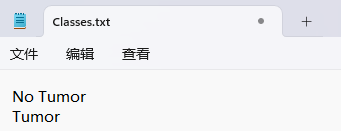

“classes.txt”定义了你的 YOLO 标签所引用的类名列表。

存放标签类别的文件的文件名为classes.txt (固定不变),用于存放创建的标签类别。